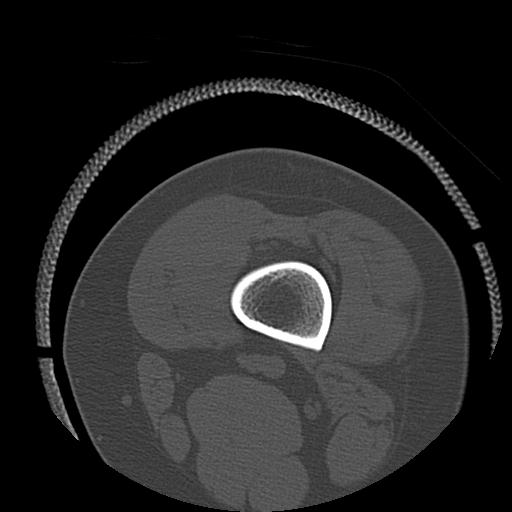

49554 3/13 膝 4R 3/16 4R 1/18 2R 78歳男性 膝蓋骨骨折